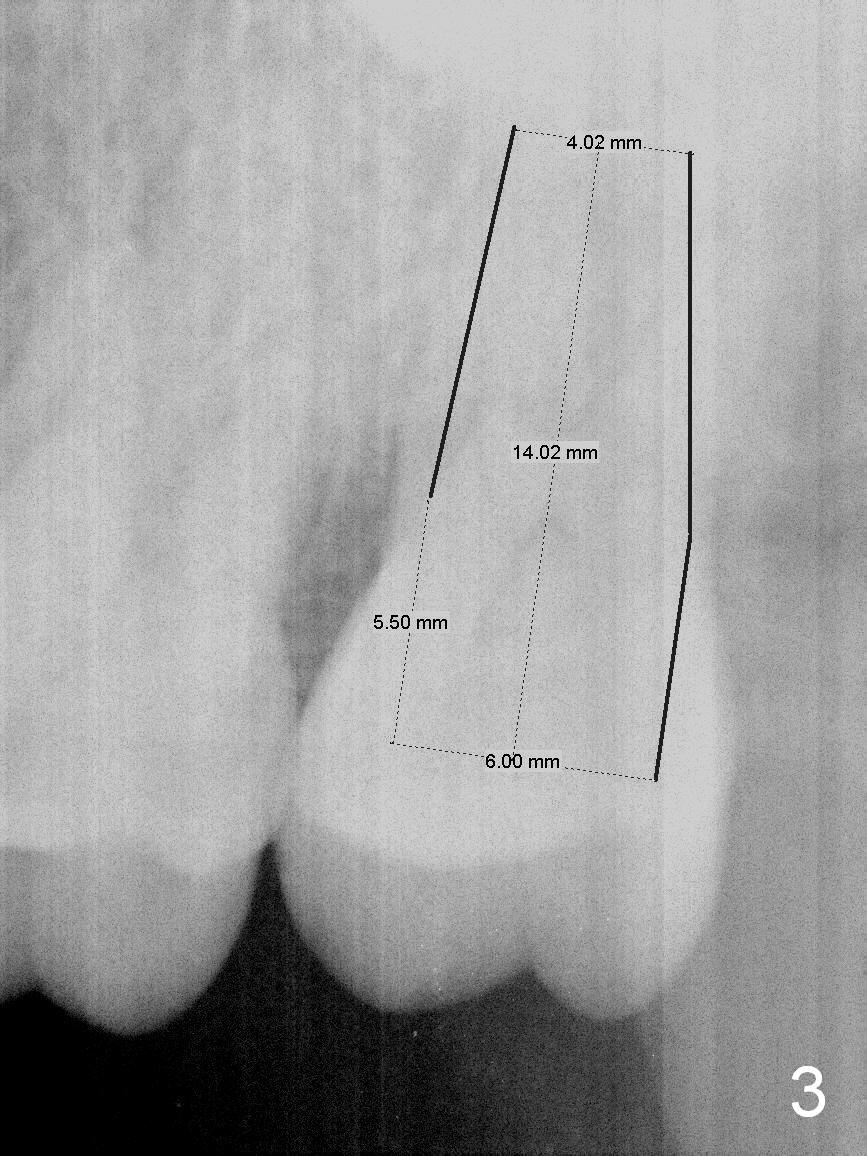

A 50-year-old man (TK) had sign & symptom of crack tooth at #15 (Fig.1) and chose to have root canal therapy done by a specialist. One month later, he returns for crown; exam reveals a crack line mesiodistally (Fig.2). The patient agrees to have immediate implant (Fig.3 design: 6x14 mm). The buccal roots fracture upon luxation. Osteotomy starts in the septum with a 2 mm pilot drill and deviates to the palatal socket, followed by 2, 3, 4 mm tapered osteotomes. A series of taps are placed: 6x17 mm one achieves stability (Fig.4). When the latter is removed, there is no sign of sinus air leakage. A 6x14 mm implant (Fig.5 I) and a 5x3 mm abutment (A) are placed. After abutment height adjustment, an immediate provisional is fabricated. Allograft with Osteogen is placed in the remaining sockets and gaps (Fig.6 *). Fig.7 shows the inner side of the provisional with double arrows indicating the dimension of the abutment, whereas arrowheads the dimension of the socket buccopalatally. When the provisional is cemented (Fig.8 P), it completely seals the socket. As long as the provisional stays, bone graft will not be lost.